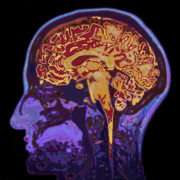

https://adolfogarcia.com.ar/wp-content/uploads/2020/10/Action-semantics-at-the-bottom-of-the-brain.jpg512428Adolfo Garciahttps://adolfogarcia.com.ar/wp-content/uploads/2020/07/logoadolfo.pngAdolfo Garcia2020-10-14 00:42:292022-05-13 22:17:35Action semantics at the bottom of the brain: Insights from dysplastic cerebellar gangliocytoma | Frontiers in Psychology